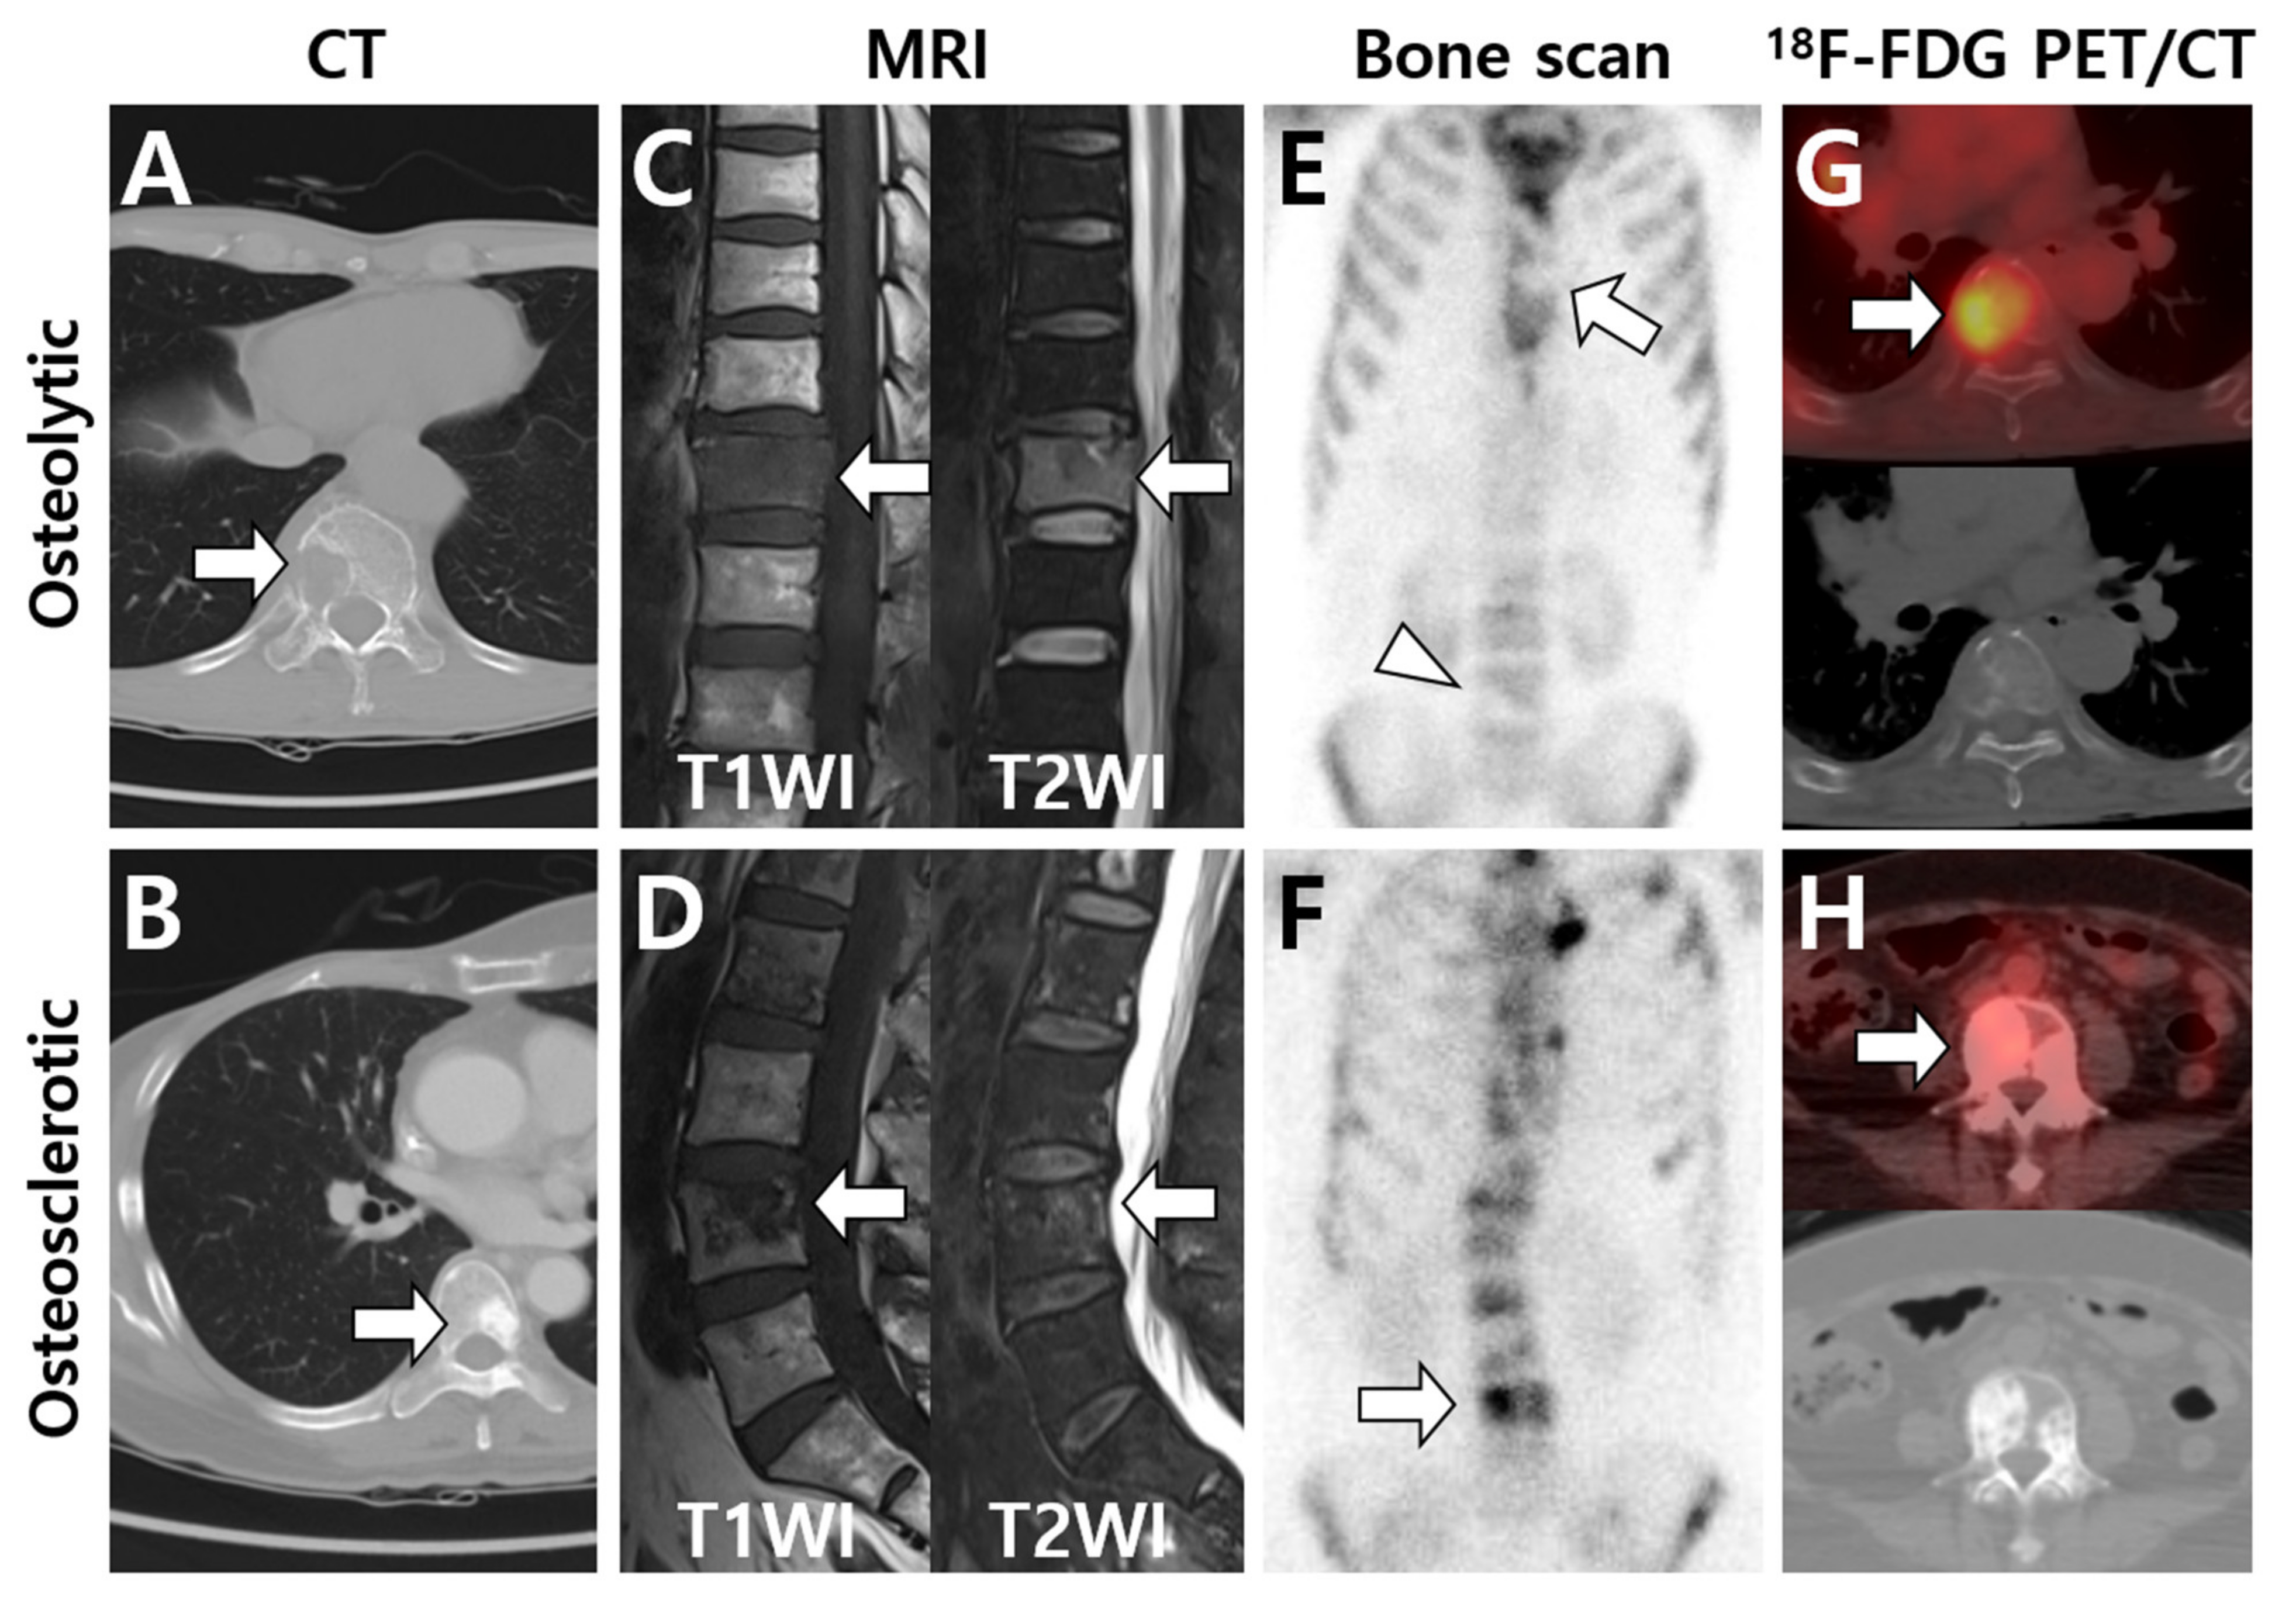

Figure 1.

Typical imaging patterns of bone metastases observed on major imaging modalities. According to computed tomography (CT) findings, osteolytic or osteosclerotic metastases are initially placed in the upper and lower rows, and imaging findings are shown for each device. (A) Osteolytic metastasis destructs cortex and cancellous bone structures and is observed as a radiolucent lesion on CT (arrow). (B) Osteosclerotic metastasis forms new bone in the marrow space and is observed as a radiopaque lesion on CT (arrow). (C,D) On T1-weighted MRI, the signal intensity (SI) is low in both osteolytic (C) and osteosclerotic (D) metastases (arrows) as the normal bone marrow is replaced with tumor cells. In contrast, T2-weighted MRI shows high SI in osteolytic metastasis (C) and heterogeneous SI in osteosclerotic metastasis (D) (arrows). (E) Osteolytic metastasis appears as decreased radiotracer uptake on bone scan (arrow and arrowhead). (F) Osteosclerotic metastasis shows increased radiotracer uptake on bone scan (arrow). (G) 18F-FDG PET/CT generally shows increased FDG uptake in osteolytic metastasis (arrow), although FDG uptake could also be affected by histologic subtypes of the primary tumor. (H) In contrast, osteosclerotic metastasis is depicted as a relatively low FDG-avid lesion (arrow) on 18F-FDG PET/CT. (A,C,E: hepatocellular carcinoma; B,D,F,H: intraductal breast carcinoma; G: lung adenocarcinoma).